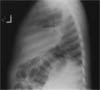

A 2 ½-year-old child is hospitalized with a 1-month history of worsening persistent cough. She was initially treated with a 5-day course of oral amoxicillin, and her symptoms abated somewhat. However, for the past week, she has experienced high fever (temperatures up to 38.3°C [101°F]) and chills associated with right-sided pleuritic chest pain.

Chest films are ordered.

The chest radiographs show alarge cavitary lesion in the rightupper chest, with air-fluid level anda bulging fissure. This finding,in a patient with persistent coughand fever, strongly suggests lungabscess, A.